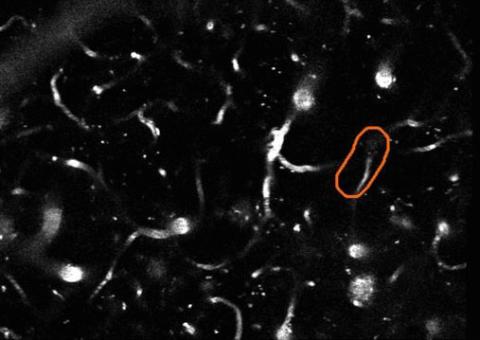

EyesOnALZ, an exciting citizen science project receiving support from the BrightFocus Alzheimer’s Disease Research (ADR) program, is the first crowd-sourced effort to gather data to help end Alzheimer’s disease (AD). The goal of EyesOnALZ is to assist researchers in the Schaffer-Nishimura laboratory at Cornell University, who are examining blood vessels in the brain for “stalls,” or clogged segments where blood is no longer flowing.

Previously, in mouse models, scientists have been able to pinpoint the link between stalls and AD progression, and even successfully reversed some Alzheimer’s symptoms by reducing the number of stalls. However, hope for a human cure could be delayed because documenting these stalls is very time-consuming: a single week’s worth of data collected in mouse models could take individual researchers an entire year to analyze.

Enter Pietro Michelucci, PhD, a cognitive scientist who believes it’s possible to solve some of the world’s greatest challenges by combining the power of computers with human intelligence. He and his staff at the Virginia-based Human Computation Center, as well as a team of collaborators worldwide, have created Stall Catchers, the first of two online citizen science games in the EyesOnALZ project. After brief coaching, a citizen scientist – any member of the public – is able to play the game by identifying tiny blood vessel blockages in videos of mouse brains. In Stall Catcher’s first 30 days, nearly 1,000 volunteers around the world produced the equivalent of 14 weeks of lab analysis.

A. Yes, we are developing a second game, which provides a complementary analysis. When you play Stall Catchers, the object of the game is to look at each movie and decide if the outlined blood vessel is either flowing or stalled. The catch is that these outlines must be created in the first place, and machines alone cannot do that. In fact, with Stall Catchers now up and running, the task of generating these outlines has become the new research bottleneck. Our new game is going to be modeled on the EyeWire project, which has been successful in segmenting retinal neurons. In this case, of course, we will be identifying blood vessel segments instead of neuronal tissue.